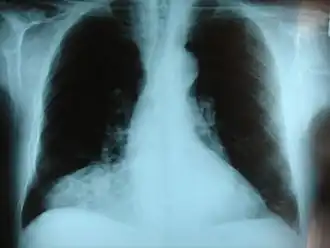

| Фронтальный рентгеновский снимок грыжи Морганьи. | |

- ретрокостостернальные (справа — треугольника Морганьи, слева — Ларрея)